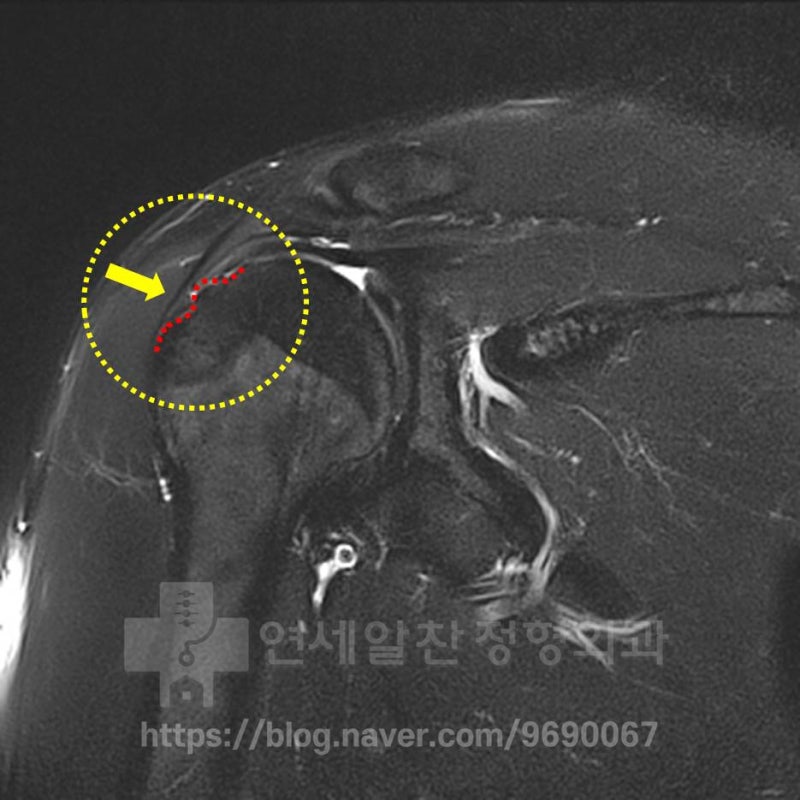

다른 MRI 를 보면 빨간색 점선으로 표시된 부위에서 대결절 부위의 불규칙한 면이 관찰되고 있습니다. 하지만 극상근의 약화는 관찰되나 파열 소견은 관찰되지 않습니다. 환자의 수상 기전과 상기의 검사들은 보았을 때 석회성 건염 보다는 대결절 골절이 발생되었고 그로 인한 불유합이 발생된 것으로 판단됩니다. 첫번째로 가장 안타까운 것은 최초 수상 당시 바로 치료를 제대로 했다면 (이정도의 손상이라면 대결절 골절에 대한 수술적 치료) 지금은 정상적으로 생활하고 운동을 할 수 있었을 것이라 생각됩니다. 그럼 이때 수술한 영상을 확인해 보겠습니다.

골편을 제거한 후 다시 극상근을 봉합한 사진이 보입니다. 여기서의 문제를 한번 살펴보면 1. 이두장건의 부분 파열이 있기 때문에 어깨회전근개파열수술을 통해 이두장건을 절제하거나 고정시켜야 했습니다. 2. 조금 더 신경써서 진단을 했더라면 석회성건염으로 진단하지 않고 상완골 대결절의 불유합으로 진단하여 불유합에 대한 수술이 진행되었다면 훨씬 더 결과가 좋았을 것이라 생각됩니다. 이유는 극상근이 파열되지 않았다는 점, 골편이 크다는 점을 고려한다면 불유합에 대한 골편 고정술 및 인대 보강술이 이 환자에게는 적합한 수술이라는 판단이 들어서 입니다. 여기서 잘 치유가 되었다면 좋겠지만 수술 다음날 찍은 MRI 상에서 봉합나사못의 해리가 관찰되었습니다. 인대가 제대로 고정이 되지 않았을 가능성이 아주 많겠지요... 환자는 그 후에도 통증이 지속되고 힘이 없어서 팔을 들어올릴 수 없었고 주사 및 약으로 버티다 최근 타 병원에서 MRI 촬영을 한 후 본원으로 오게 되었습니다. 그렇다면 내원 당시의 상태를 확인해 보겠습니다.